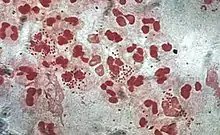

Ofte gramnegative, stavformede bakterier og svampe, som kan være svære at dyrke:

- Staphylococcus aureus

- Streptococcus